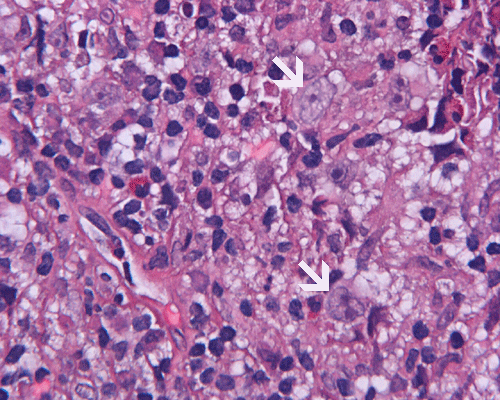

Paraffin sections: The entire volume of the tissue is made up of a granulomatous inflammation with poorly formed granuloma (Panel F, G, and H). The density of the lymphocytes is variable in different areas. In some areas, there is a rather intense lymphocytic infiltration accompanied by scant atypical cells with enlarged nulcei and prominent nucleoli (arrows in Panel I and J, Panel J is a higher magnification of Panel I). These atypical cells are quite easy to be missed. No microorganisms were identified by acid fast stain, PAS stain or GMS stain. The lymphocytes but not the atypical cells are positive for CD20 (Panel K) or CD3 (Panel L). The granulomatous background is strongly positive for CD68 (Panel M). Only rather faint positive staining for placental alkaline phosphatase (PLAP) is demonstrated and the interpretation is difficult as they are present in areas with crush artifact (Panel N). Many of the large, atypical cells are positive for CD117 (c-kit) (Panel O).

Intracranial germinoma is histologically identical to ovarian dysgerminoma and testicular seminoma. There is a tendency to infiltrate adjacent structures and to spread throughout the ependyma, the ventricular system and subarachnoid spaces. Microscopically, they consist of nests, lobules, cords, and/or sheets of large round tumor cells with well-defined borders, clear to pale cytoplasm with artifactual vacuolization, round and centrally located nuclei with open chromatin and prominent round or bar-shaped nucleoli. The cytoplasm is glycogen-rich, making these cells periodic acid-Schiff (PAS)–positive and diastase sensitive. These tumor cells are mitotically active. Atypical mitosis, however, is not a common finding. Necrosis is usually not prominent. In the most classic histologic picture, clusters and cords of large germinoma cells are separated by a dense, lymphocytic infiltration admixed with some macrophages and a delicate fibrovascular network. Plasma cells may be found. At medium-power magnification with hematoxylin and eosin stain, the contrast between the smaller, darkly staining lymphocytes and the larger, pale staining cytoplasm of neoplastic cells is virtually pathognomonic. The amount of inflammatory cells can have wide variations among different tumors. In some occasions, the large germinoma cells are difficult to be found and the overall picture may suggest a lymphoma. Syncytiotrophoblastic cells can also be present. These cells should not be mistaken as evidence of choriocarcarcinoma.

Granulomatous changes are common findings in germinomas and intracranial germinomas follow this general trend 3, 4, 5. It can be extensive. This feature is particularly problematic in neuropathologic when stereotactic biopsy is performed and the amount of tissue available for examination is limited as illustrated in this case. During intraoperative consultations, a frozen section diagnosis of granulomatous inflammation should prompt additional sampling as isolated granulomatous inflammation of infectious origin and sarcodosis are quite uncommon in the pineal gland.